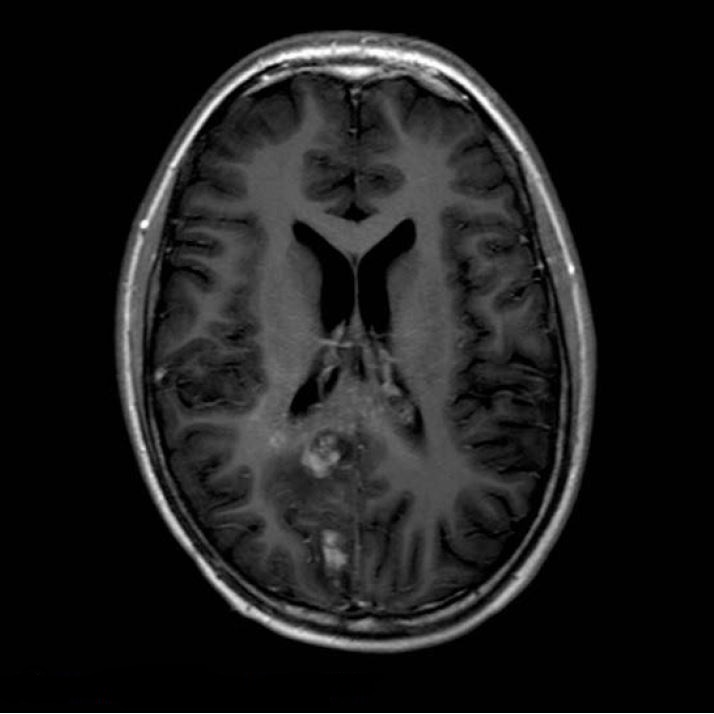

Контрольні МРТ-дослідження залишалися стабільними до липня 2011 року (відразу до кінця супутньої хіміотерапії) (рис. 3 і 4). Потім було проведено додаткове обстеження МРТ (через 4 тижні) з перфузією та МРС.

Рисунок 3 T2WI, липень 2011